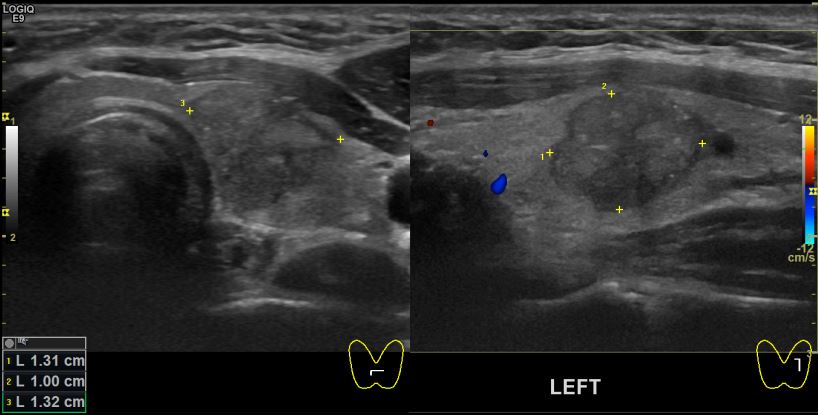

아산유외과 개원후42번째 갑상선암 진단

상기환자 30대 여성분으로 건강검진상 갑상선의 결절있어 경과관찰로 내원하시어 의심스러운부분 세침검사 시행하여 갑상선암 진단되었읍니다